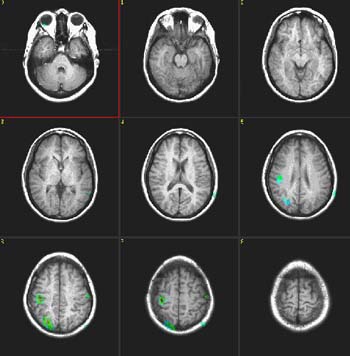

Fluency of Verbs

| Subject |

Right handed, 24 year-old woman |

| Paradigm |

ON: Generate verbs related to nouns (objects)

OFF: Count the letters of presented words |

| Statistics |

| Statistical method |

P Value |

Z score |

| T-Test |

0.0001 |

3.8 |

|

| Images |

| Activation |

Broca's area and left SMA are depicted. Some activation appears in the left hippocampal formation and visual areas. This last activation could be explained as the effect of picturing the objects given during the "ON" condition. There is also activation in the right cerebellum and left inferior temporal gyrus.